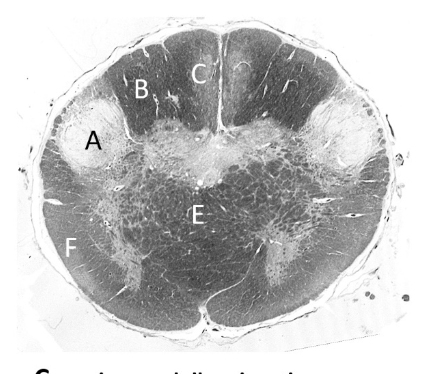

at what level is this?

lower medulla

what is a?

pyramid/ pyramidal tract (lm)

what is b?

spinal trigeminal nucleus (lm)

what is c?

trigeminal tract (lm)

what is d?

nucleus gracilis

what is e?

nucleus cuneatus (LM)

what is f?

internal arcuate fibres

what is g?

medial lemniscus (lm)

what is h?

inferior olivary nucleus (lm)